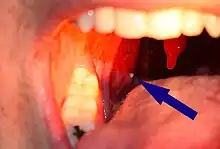

| A tonsillolith lodged in the tonsillar crypt | |

A tonsillolith protrudes from the tonsil

Large tonsillolith half exposed on tonsil